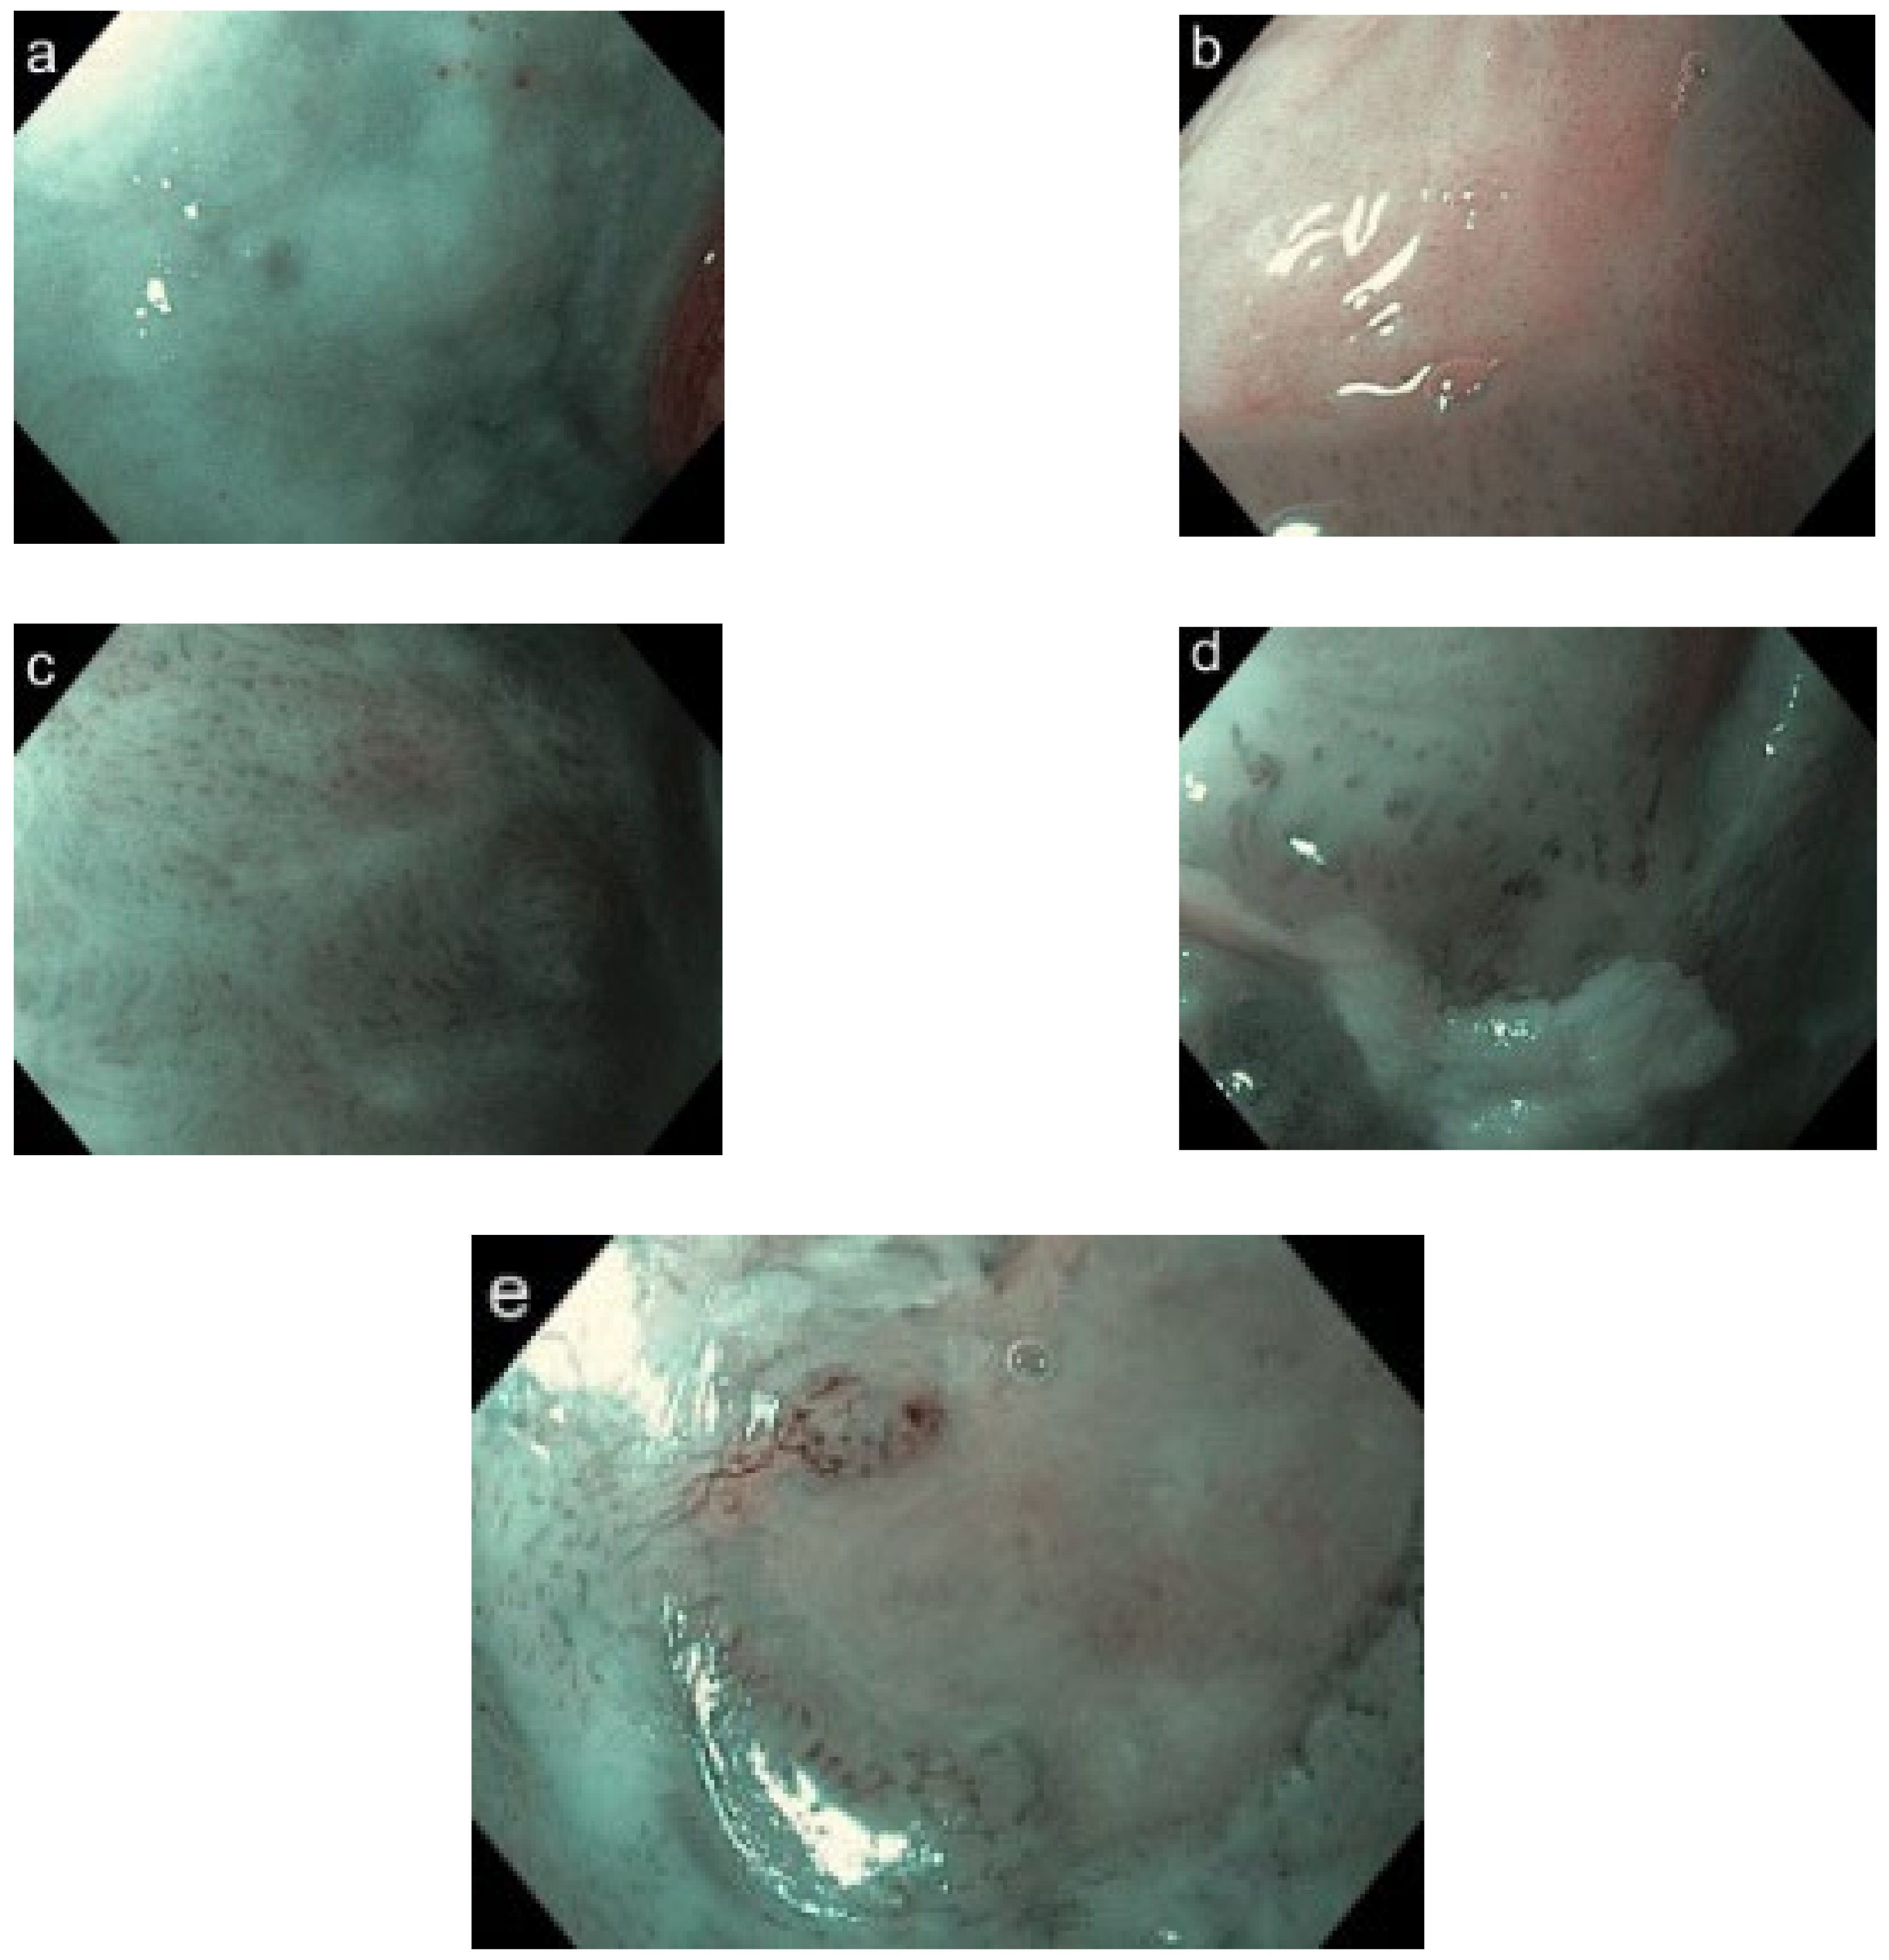

Based on the classification by Vu et al., the IPCL classification of the oral mucosa was conducted by modifying Inoue’s classification, which consists of four progressive increases in the IPCL pattern type with a 5th (type 0) when IPCL patterns are not visualized because of thick keratosis or oral leukoplakia: type I (physiological arborization of IPCL), type II (meandering or dilated IPCL), type III (convoluted/winding and/or elongated IPCL), and type IV (complete loss of organization/annihilation of the IPCL) (Figure 4a–e) [30,31].

Figure 4. Five types of IPCL classification. Types 0 (a), I (b), II (c), III (d), and IV (e).

The IPCL showed favorable reliability in terms of Cohen’s Kappa index. Intra-observer reliability was 0.81 (95% CI: 0.69–0.93), and inter-observer reliability was 0.75 (95% CI: 0.61–0.88) (Table 3). Twelve (75.0%) OLP lesions were low-grade (I–II) IPCL patterns, and four lesions (25%) were type III IPCL (Figure 6a). Clinical oral leukoplakia showed various type of IPCL including nine (29.0%) type 0; 14 (45.1%) type I; three (9.7%) type II; three (9.7%) type III; and two (6.7%) type IV (Figure 6b). Owing to the thickness of the oral leukoplakia, it was difficult to observe the IPCL directly. IPCLs were therefore observed at the borders of the lesions. There were five (16.1%) non-homogeneous lesions for all clinical oral leukoplakia types, 80% of which had type III or IV IPCL. For pathological diagnosis, the three type III and two type IV IPCL showed moderate epithelial dysplasia and proliferative verrucous leukoplakia, respectively. OSCC was composed of five (38.5%) type III IPCL and eight (61.5%) type IV IPCL. OSCC showed a clearly advanced IPCL pattern (Figure 6c). The distribution of IPCL varied according to disease. There were statistically significant differences (Kruskal–Wallis test, p < 0.001). Depending on the site of the mouth, the loops were found in parallel or perpendicular locations in relation to the surface. The IPCL appeared as scattered brown dots in the perpendicular position, while they appeared as waved lines in parallel positions (Figure 4e). Thus, types III and IV IPCL are related to the malignancy of the lesion